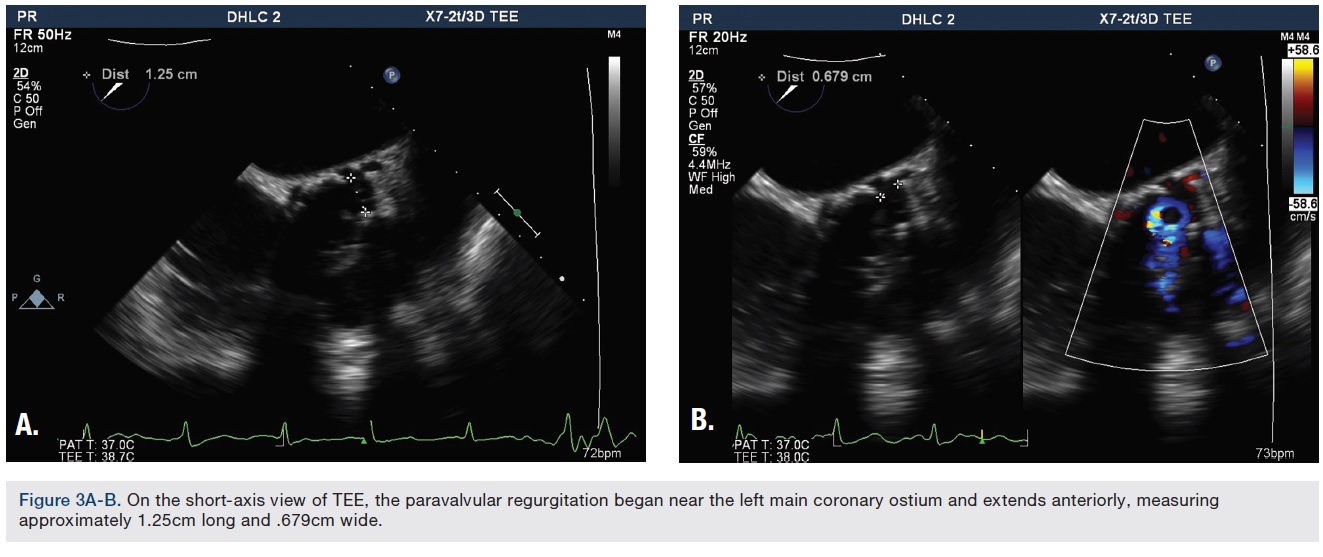

The procedure was performed under deep sedation with use of intravenous (IV) propofol. Transesophageal echocardiography (TEE) was utilized to assist in the closure of the aortic paravalvular leak (PVL). TEE confirmed a bioprosthetic aortic valve with mild central intrinsic regurgitation, and moderate to severe paravalvular regurgitation (Figure 1A-B). The paravalvular regurgitation was found at the lateral aspect of the aortic annulus (Figure 2).

The paravalvular regurgitation began near the left main coronary ostium and extended anteriorly, measuring approximately 1.25cm long and .67cm wide (Figure 3A-B). Both right femoral and right radial accesses were obtained using a 6 French sheath. The aortography, performed via a right radial approach, also demonstrated the paravalvular leak (Figure 4). After crossing the PVL with a .035-inch Glidewire (Terumo Interventional Systems), the guide catheter was unable to advance through the PVL over the .035-inch Glidewire, despite multiple attempts via the femoral approach with different catheters. Attempts were made using a 6 French multipurpose guide catheter, a 5 French Judkins right (JR)4 guide catheter, a mother-daughter technique with a multipurpose guide and a diagnostic catheter, a 6 French, 90cm Destination sheath (Terumo), and a 5 French, 90cm Ansel sheath (Cook Medical).